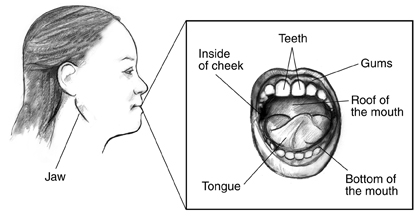

Too much glucose, also called sugar, in your blood from diabetes can cause pain, infection, and other problems in your mouth. Your mouth includes

your teeth

your gums

your jaw

tissues such as your tongue, the roof and bottom of your mouth, and the inside of your cheeks